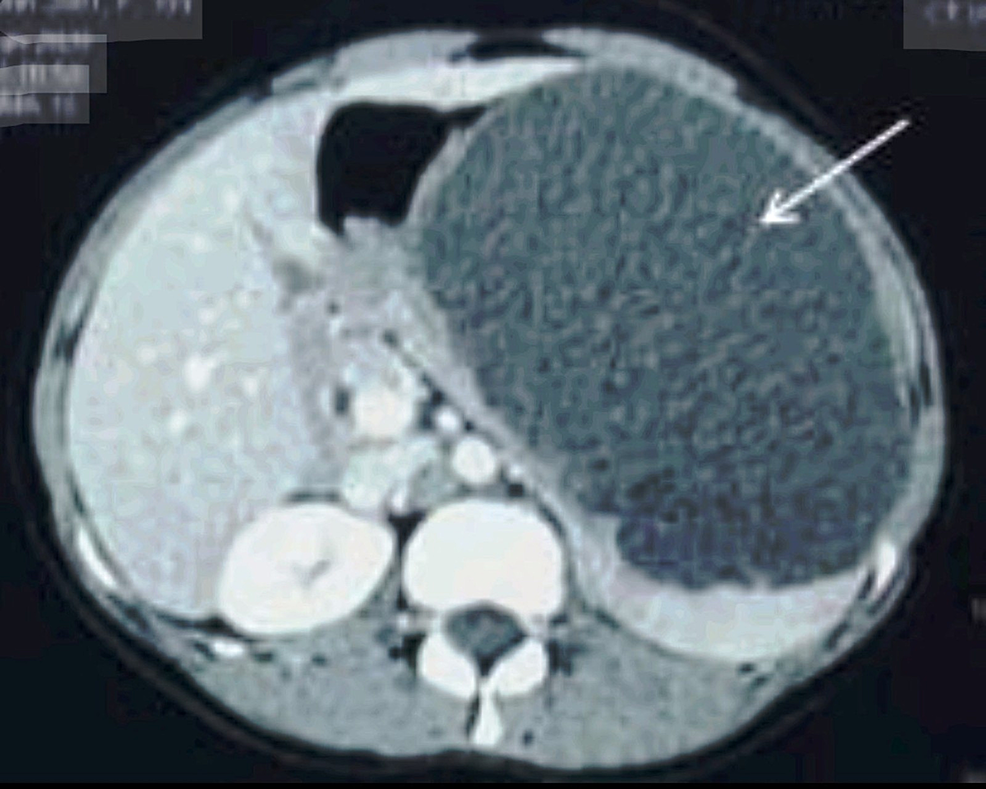

Peliosis of spleen. Contrastenhanced CT shows multiple hypodense Lesion On Spleen There are a number of splenic lesions and anomalies: Learn about the spleen, a small organ that stores and filters blood and makes white blood cells. These usually manifest as splenomegaly. There are many different kinds of masses and lesions of the spleen. Cystic lesions of spleen have many causes, some of which are outlined above. Spleen cancer is a. Lesion On Spleen.

Peliosis of spleen. Contrastenhanced CT shows multiple hypodense Lesion On Spleen Find out what conditions and. There are many different kinds of masses and lesions of the spleen. Cyst of the spleen can be something you’re born with or. Learn about the types, symptoms,. Cystic lesions of spleen have many causes, some of which are outlined above. Spleen cancer is a rare tumor in the spleen, often caused by cancer spreading. Lesion On Spleen.